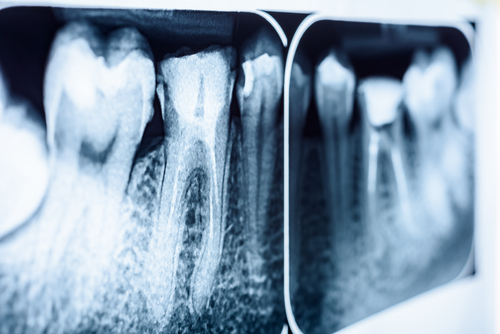

This tool, called a Peizotome, is a small device with a thin blade that’s cooled with water. The blade slides between the tooth and the surrounding bone. Instead of grinding away bone with a bur, the blade gently separates the tooth from the ligament that holds it in place (the periodontal ligament).

By slowly working the blade down along the root and moving it up and down, the tooth loosens naturally. Once it’s freed, we simply grasp it and remove it with very minimal force. It’s a much gentler, less traumatic way to perform an extraction.

This technique is especially valuable for front teeth, where preserving the bone is critical for aesthetics. It takes a little longer than using a bur, but it maintains far more bone, which is important for implants and cosmetic outcomes.